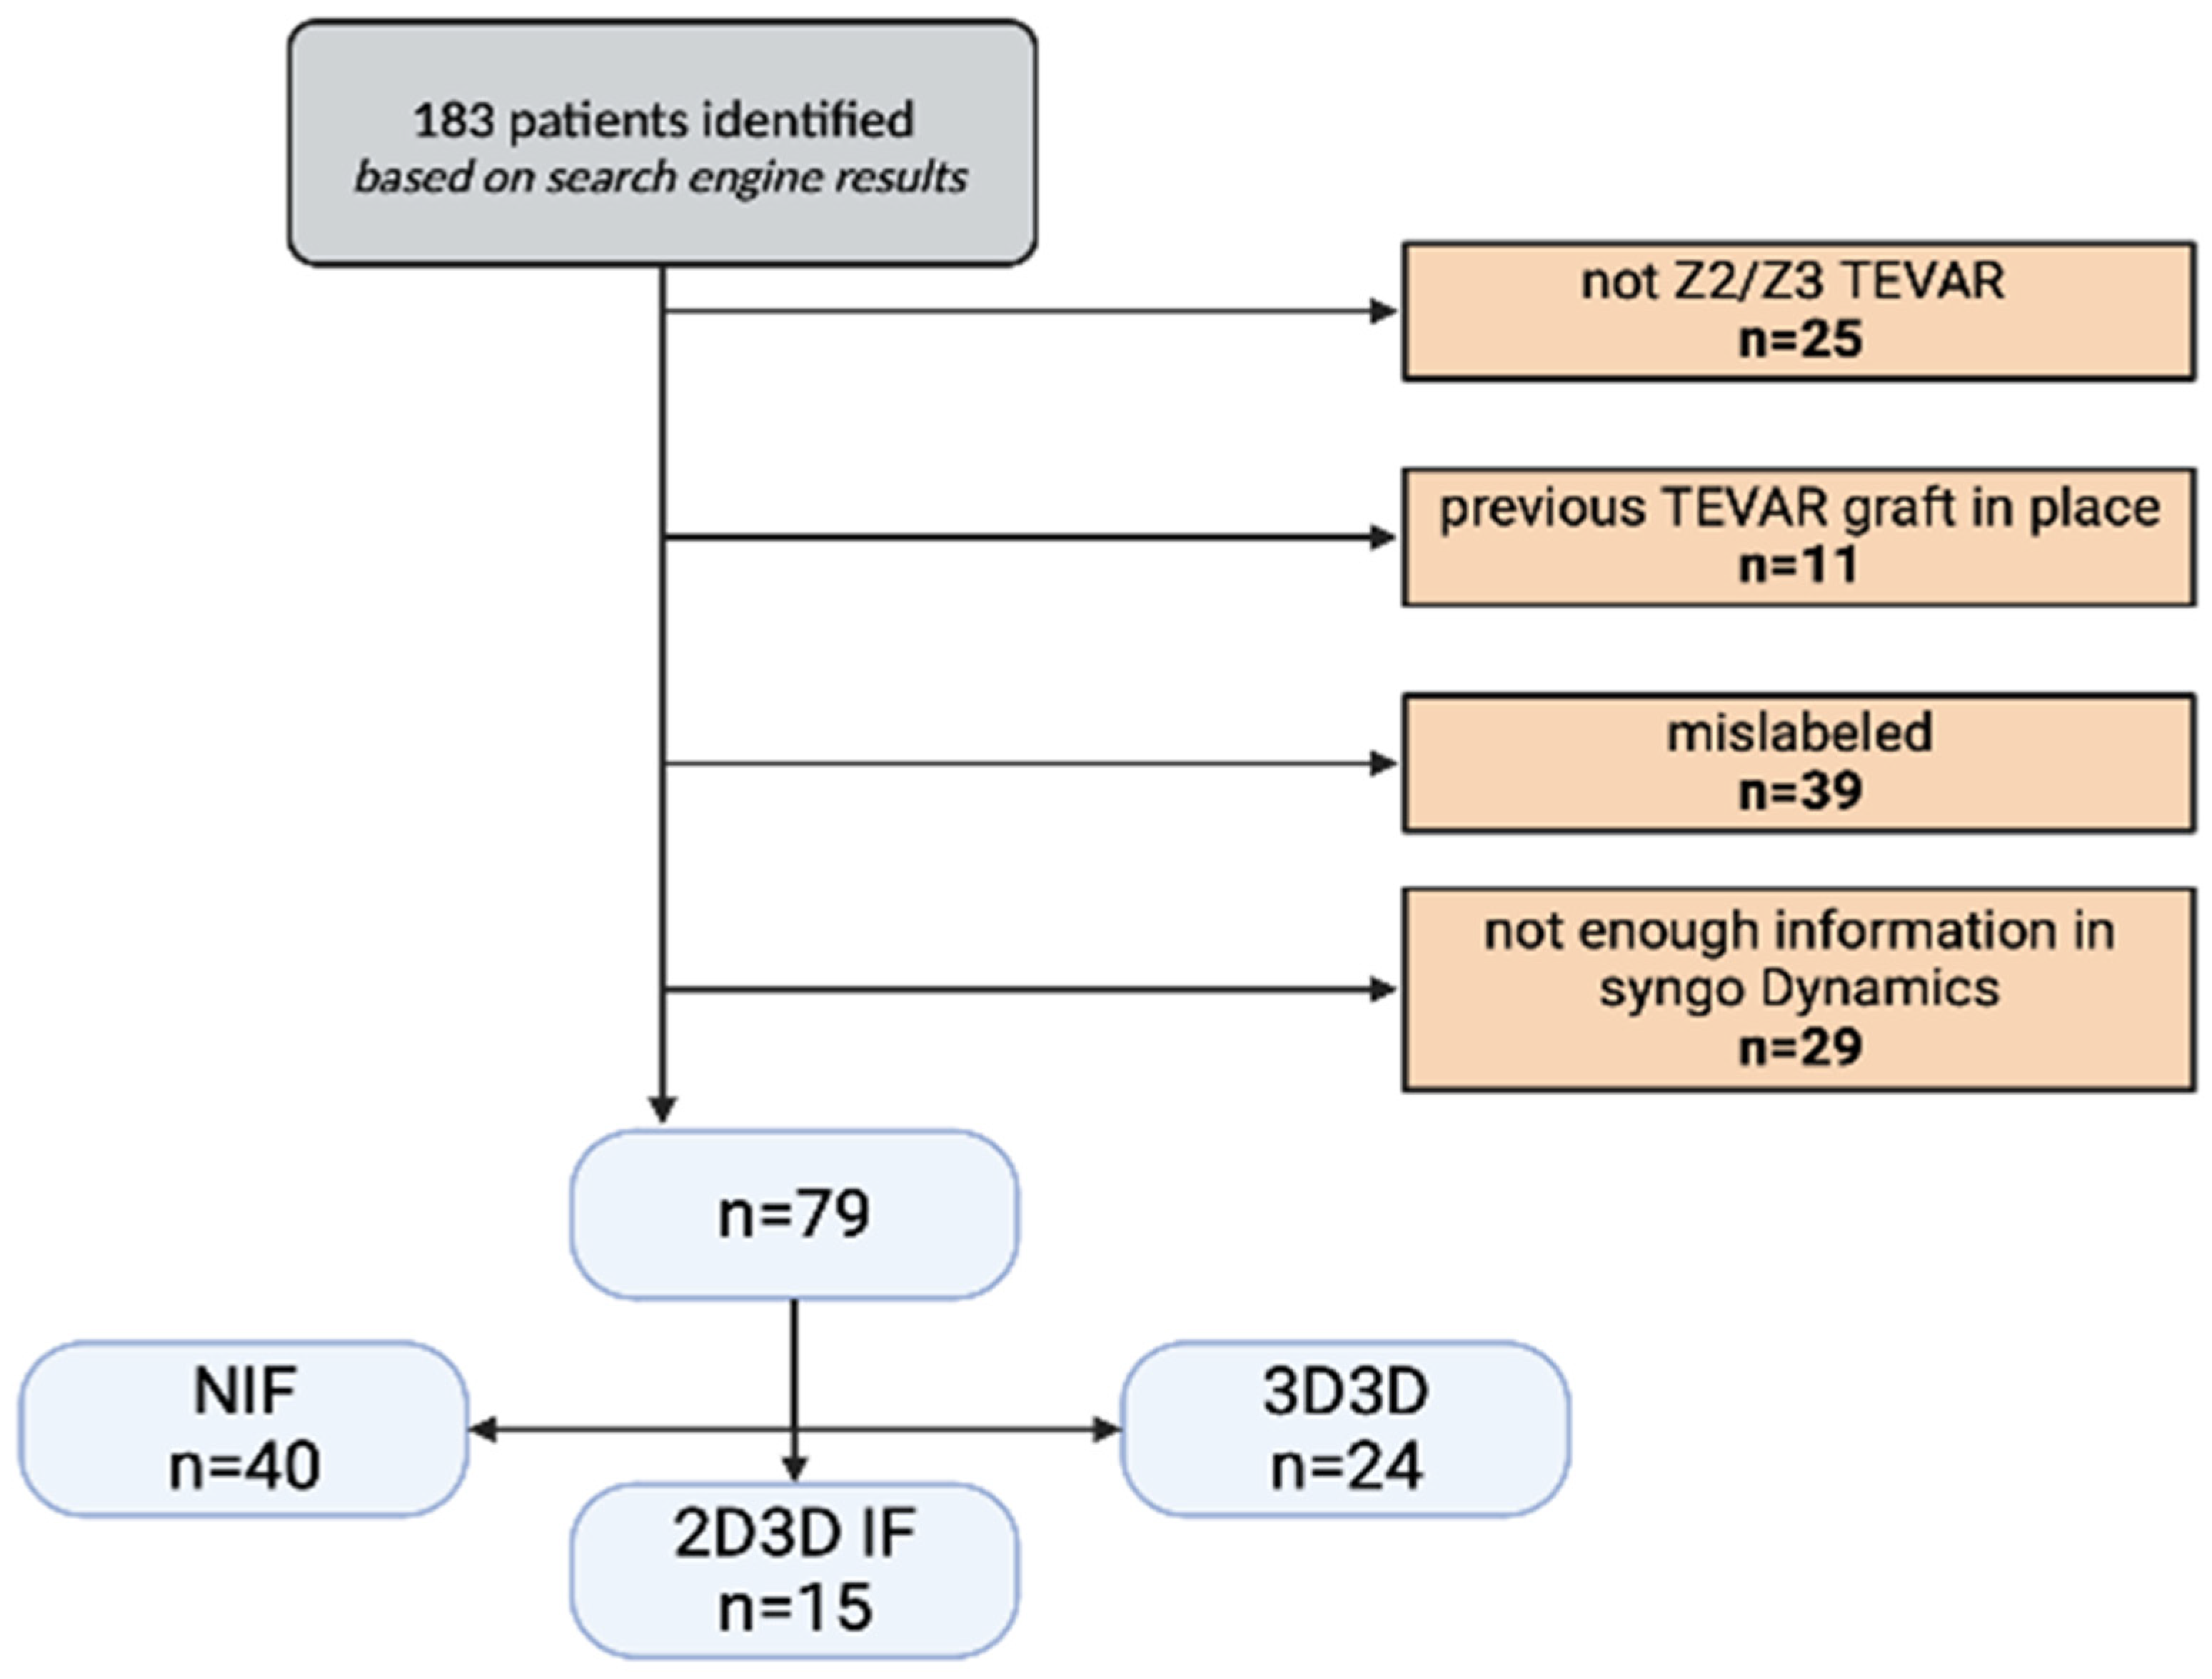

2.1. Study Design

3. Results

Z3 TEVAR Subgroup